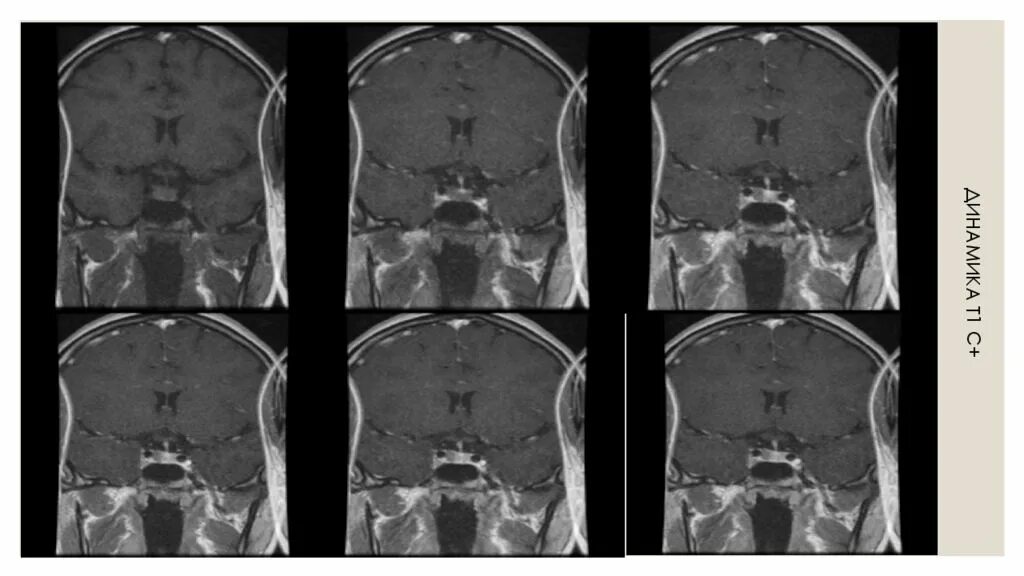

Гипофиз мрт норма